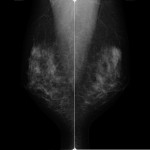

乳房撮影(マンモグラフィ)

マンモグラフィとは

マンモグラフィーとは、乳房のX線撮影です。乳がんの初期症状のひとつである、微細な石灰化を見つけ出すことにとても優れた検査です。また、触ってもわからないようなしこりを、写し出せることもあります。そのため、病変がある方の検査としてだけでなく、乳がん検診の一つとしても行っています。

検査内容

検査時間は、およそ10分程度です。画像を診断するときは、左右の乳房を比較するため、基本的に両方の乳房を撮影します。撮影方法は、上下にはさむCC撮影注1と斜め横からはさむMLO撮影注2の2種類です。左右合わせて、4枚撮影します。また場合によっては、拡大撮影など追加の撮影を行うことがあります。

注1:CC撮影:頭尾方向撮影(craniocaudal:CC)

注2:MLO撮影:内外斜位方向撮影(mediolateral oblique:MLO)

撮影方法

乳房は、専用の透明な板ではさんで撮影します。乳房を薄く広げることにより、より鮮明な画像になり、病変があったときに見つけやすくなります。さらに、乳房が薄くなるほど、被ばくのX線量は少なくなります。痛みを感じる方は多いかもしれませんが、圧迫はとても重要なことです。無理のない範囲で、ご理解とご協力をお願いします。

当院の特徴

撮撮影は女性の技師が担当しておりますので、安心して受診してください。より適切な撮影を行うため、NPO法人日本乳がん検診精度管理中央機構による認定試験を受講した認定技師がおります。同機構の施設認定も取得しており、3年ごとに更新しています。装置はFPD注3搭載のため、高画質化と被ばく低減が可能になりました。そして、3Dマンモグラフィー(トモシンセシス注4)機能を追加したことにより、正常な乳腺と病変の重なりを解消し、より精度の高い情報を得ることができます。またマンモトーム生検注5も行っています。

注3:FPD:平面型検出器(Flat Panel Detector:FPD)

注4:トモシンセシス:乳房を異なる角度から複数撮影をして、その画像を再構成して乳房内の断層像を得ること。1回の撮影で25度の角度を移動しながら撮影します。